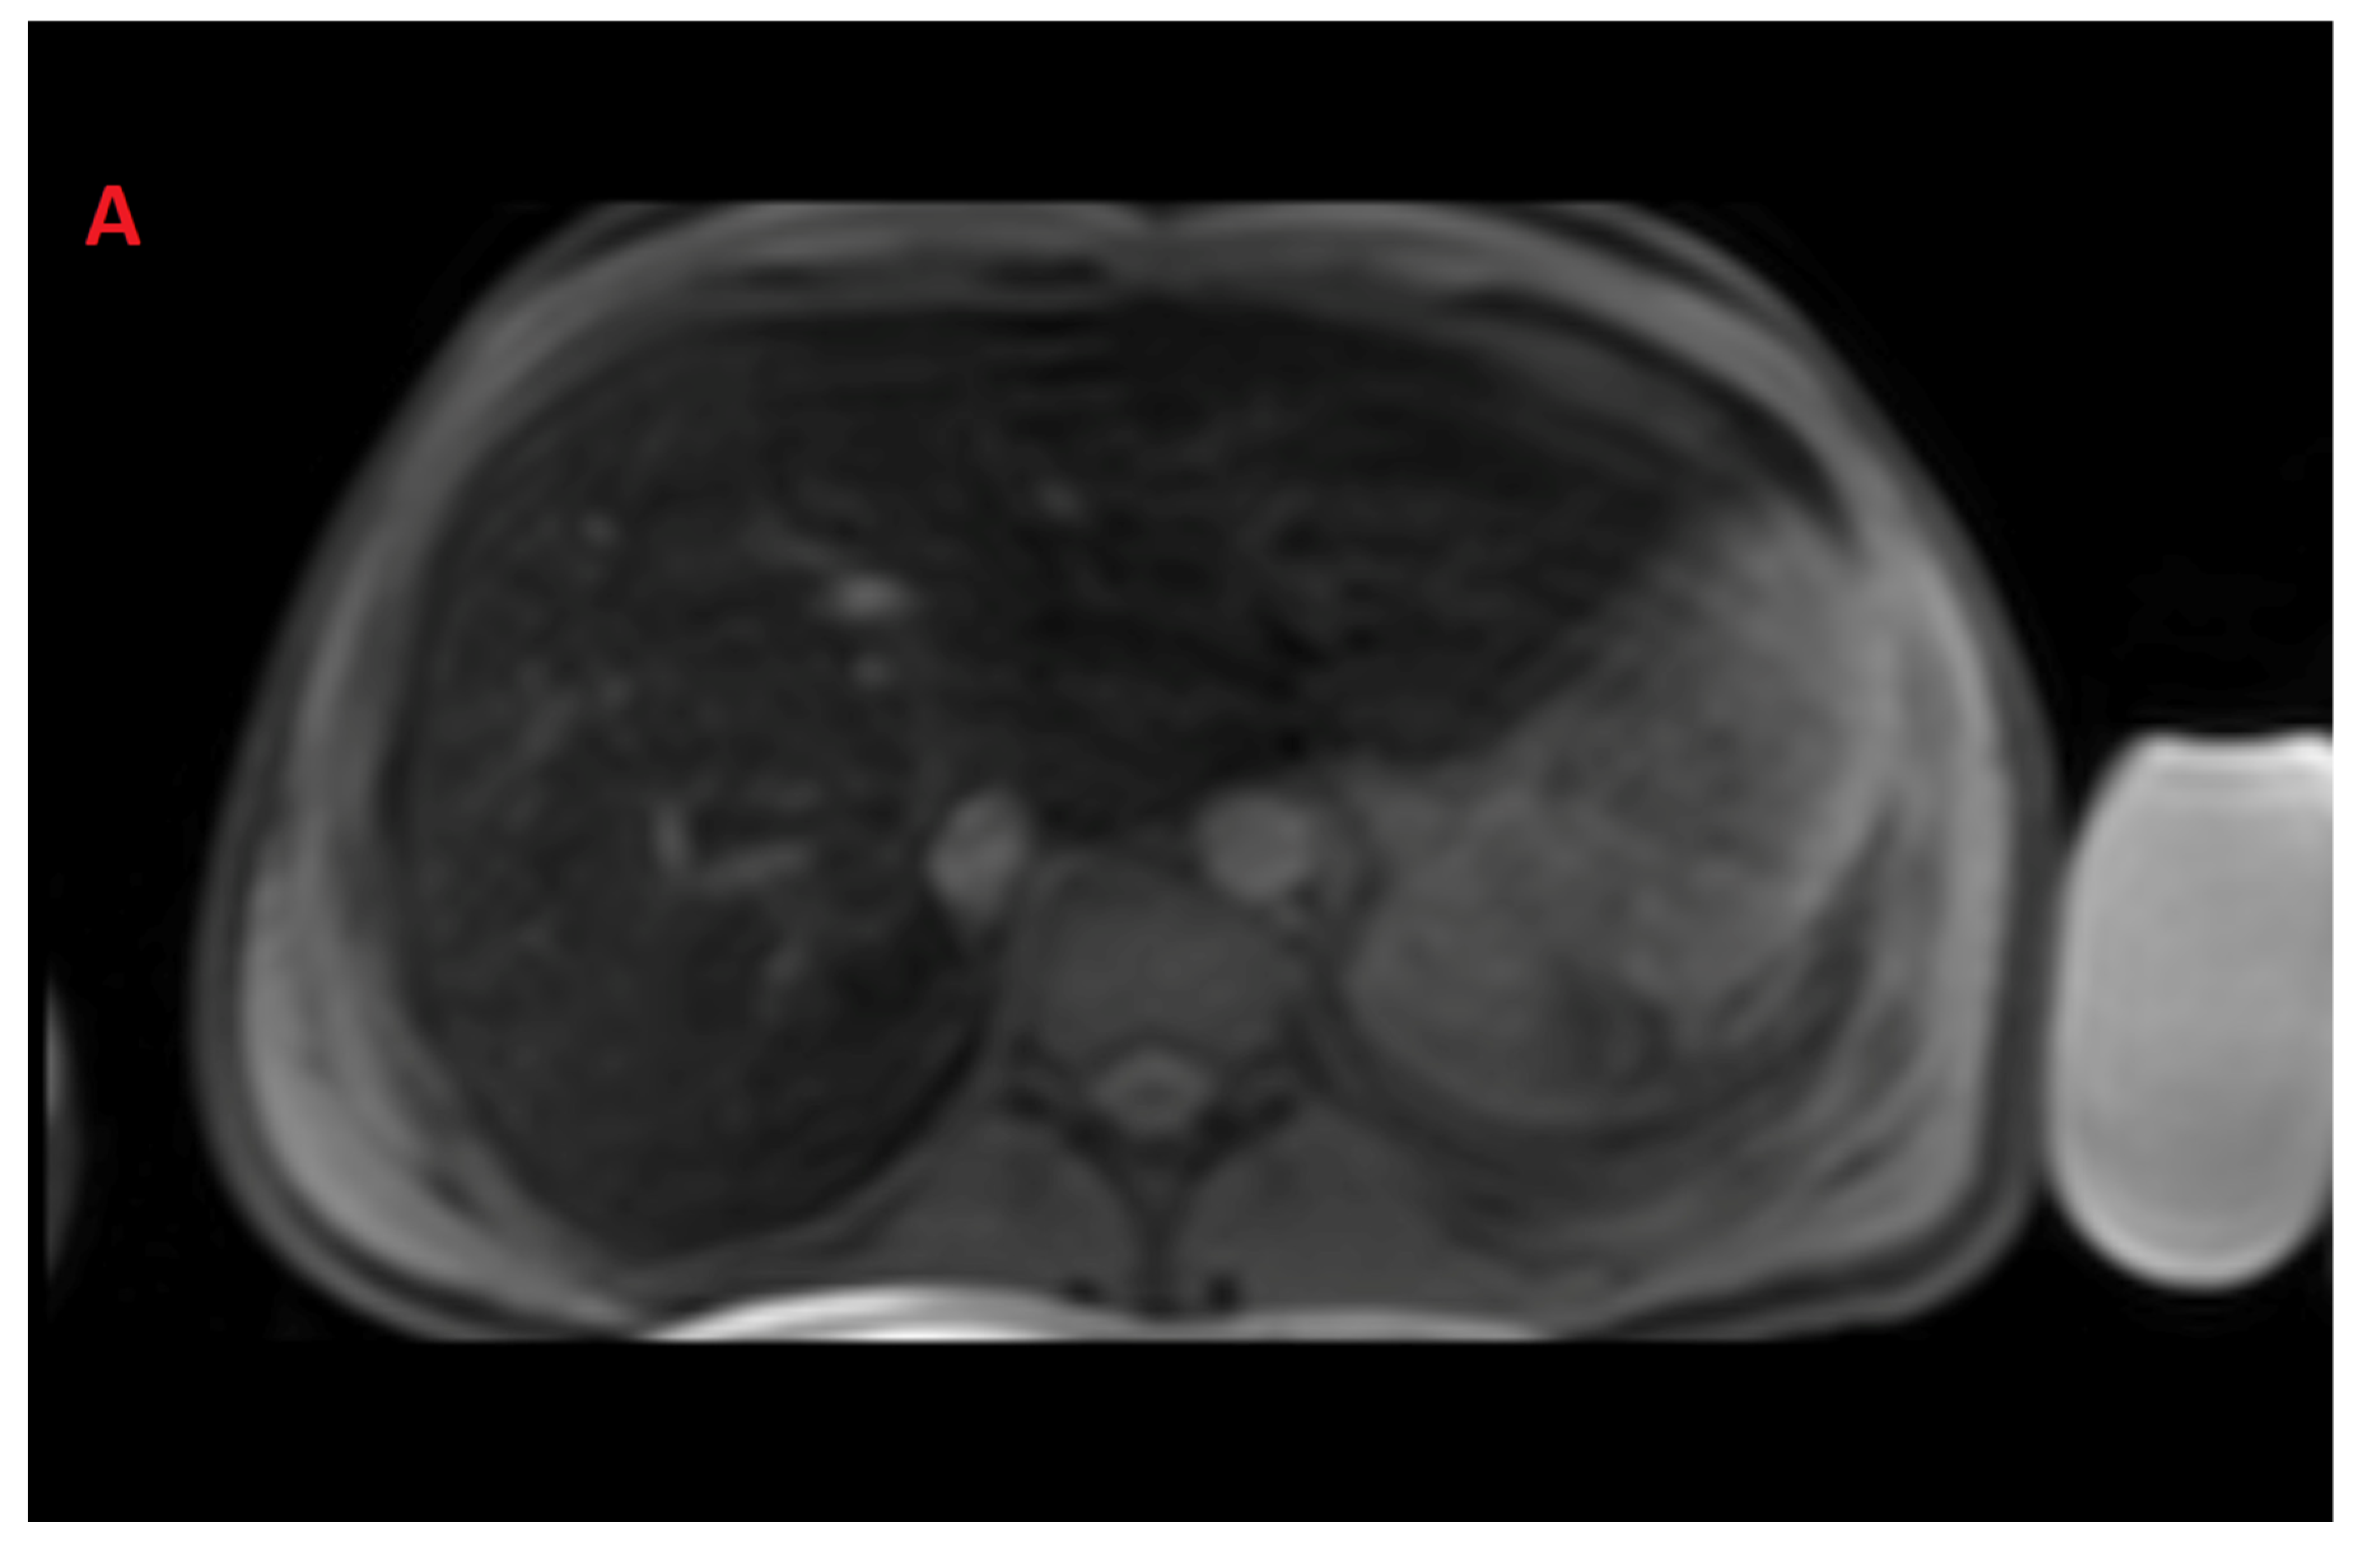

The mean value of LIC R2 at the first scan of the subjects was 14.8 ± 11.9 mg/g (range: 1.1 mg/g to 43 mg/g), and the mean value during last follow-up was 13.2 ± 11.7 mg/g (range: 1.4 mg/g to 43 mg/g). The average rate of change of LIC as determined by R2 (∆LIC R2) was −0.0043 ± 0.0214 mg/g per month. Representative images from anonymized FerriScan® reports of two different patients at two time points are shown in Figure 1. The descriptive statistics for the rate of change of LIC calculated by the two methods are described in Table 3.

Figure 1.

Representative images from anonymized FerriScan® reports of two different patients in the upper (A,B) and lower panels (C,D) at two time points (color scale shows the range of R2).